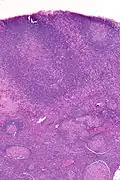

Micrograph of a lymph node biopsy showing progressive transformation of germinal centres. H&E stain.

Micrograph showing PTGCs. H&E stain.

PTGCs is characterized by:[1]

• follicular hyperplasia (many follicles),

• focally large germinal centres, with poorly demarcated germinal centre (GC)/mantle zone interfaces (as GCs infiltrated by mantle zone lymphocytes), and

• an expanded mantle zone.